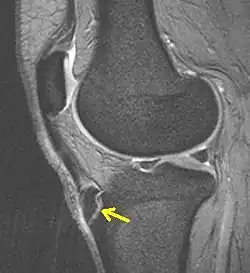

![]() Obraz MRI T2-zależny kolana w chorobie Osgooda i Schlattera u dorosłego (po przebyciu choroby); strzałka wskazuje ektopowy fragment kości utworzonej w miejscu rozdarcia więzadła rzepki(typ III) | |

Może występować jedno- lub dwustronnie (częściej jednostronnie). Choroba trwa od kilku miesięcy do kilku lat, w zależności od typu. Choroba polega na uszkodzeniu w różnym stopniu jądra kostnienia nasadowej części guzowatości kości piszczelowej. Elementami towarzyszącymi chorobie jest obrzęk i wzmożone unaczynienie więzadła rzepki, chrząstki powlekającej jądro kostnienia, tkanek kaletki podrzepkowej głębokiej. Typ I – wewnętrzne uszkodzenie jądra kostnienia bez naruszenia ciągłości chrząstki, w której jądro się znajduje. Typ II – uszkodzenie jądra kostnienia ze złamaniem chrząstki poza polem przyczepu więzadła rzepki. Typ III – uszkodzenie jądra kostnienia ze złamaniem chrząstki w polu przyczepu więzadła rzepki.